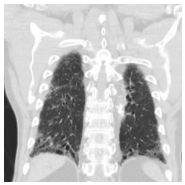

17. 50 y/o Female, Progressive dyspnea and cough for months.